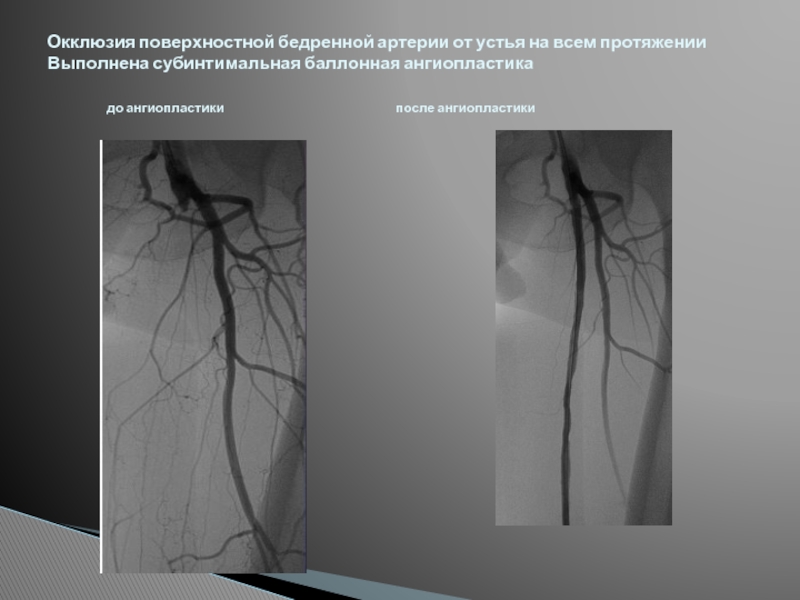

Хроническая окклюзия артерий: причины, симптомы и лечение